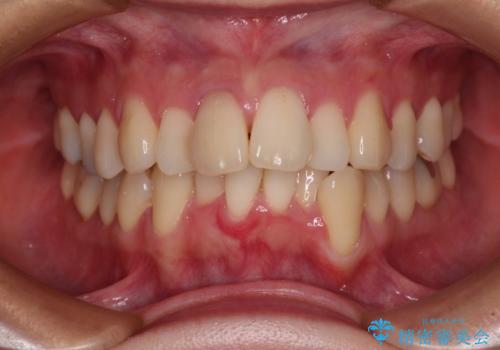

- 八重歯と上の前歯が出っ歯になっていることを気にして来院された患者様です。

横から見た際の口元の飛び出した印象も改善したいとのことで、上下左右の第一小臼歯4本を抜歯し、ワイヤー装置にて抜歯矯正を行うこととしました。

前歯の変色している歯は、神経組織が壊死していたため、矯正治療前に根管治療を実施し、矯正治療後にオールセラミッククラウンにて補綴治療を行うこととしました。

順調に歯が動き、補綴治療も含め2年弱で治療を終えることができました。